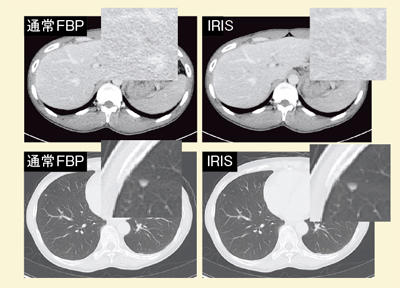

FBP法とIRISによる症例画像の比較では,IRISの画像の方がノイズを低減できており,シャープに描出されている(図4)。DEイメージングにおいて,Two-material decompositionで骨と造影剤を分離する場合でも,FBP法よりもIRISの方が良好に分離可能となる(図5)。

![]() 図4 FBP法とIRISの画像の比較 |